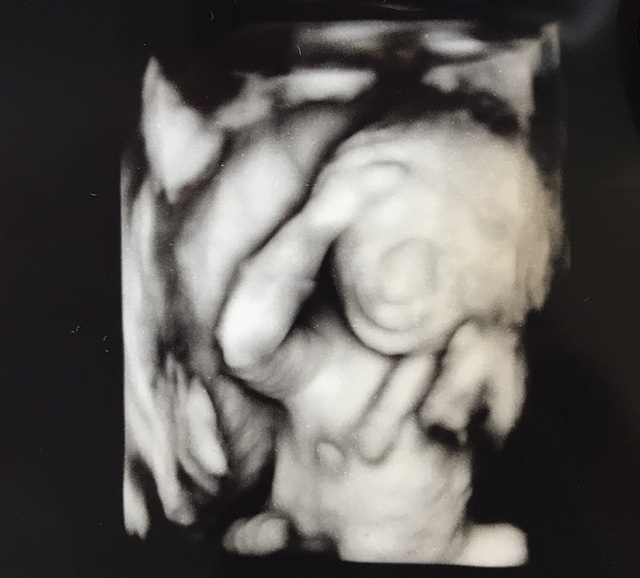

19週1日(19w1d・男の子)|きうらよしこ さん(35歳)

エコー写真撮影時のエピソード:

初めて4Dエコーで我が子を見ることができました。普通のエコーに比べ、鮮明に顔を見ることができ、更に愛しく思えたのを記憶しています。悪阻がきつかったですが、時折写真を眺め、悪阻があるってことは子どもが元気に育っている証拠なんだなぁ等気持ちが前向きになり、どんなお顔なのかな?等話しかけたりしていました。主人も写真を見返しては、どっちに似てるんだろうなぁと嬉しそうに話していました。食事面に関しては、幸い食べ物は何でも食べれたので、あまり神経質にならず好きなものを口にしていました。ですが、出来るだけ自炊をし、赤ちゃんに良いものをと色々ネットで調べて作ったりしました。自分が口にしたものがそのまま我が子へ繋がってるんだなぁ、しっかり栄養とってね等話しかけたりもしてましたね。